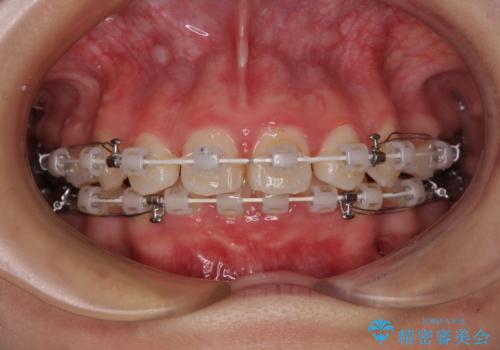

- 矯正装置

- 審美装置

飛び出した前歯はしっかりと引っ込み、横顔の印象が大きく変化しました。